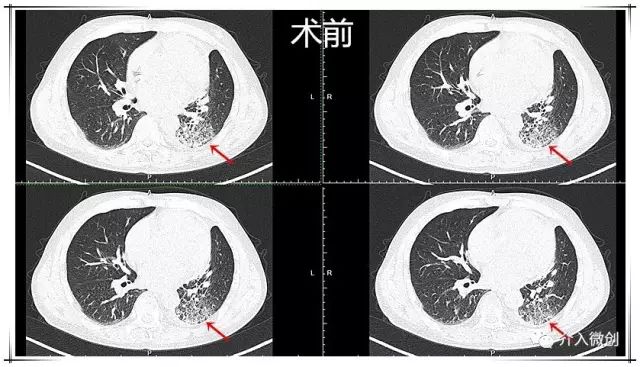

肺部CT显示右上肺恶性肿瘤并右肺门、纵膈淋巴结转移

肺窗

动脉期

静脉期